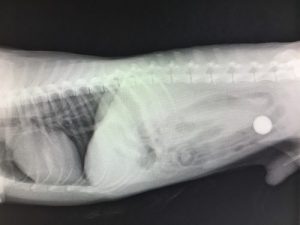

消化管内異物の緊急手術